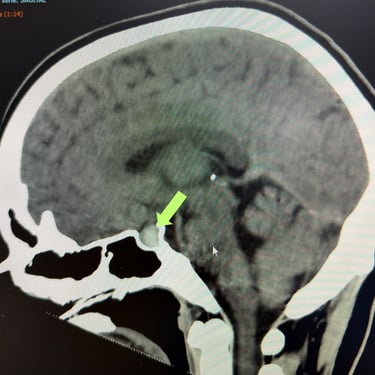

Tumor Selar Hemorrágico: Tratamiento Endoscópico Transesfenoidal.

El tumor selar hemorrágico, también conocido como apoplejía hipofisaria, es una urgencia neuroquirúrgica que puede manifestarse con cefalea intensa, alteraciones visuales y compromiso hormonal agudo. El abordaje mediante cirugía endoscópica transesfenoidal permite un acceso directo y mínimamente invasivo a la región selar, facilitando la evacuación del componente hemorrágico y la resección del tumor. Esta técnica ofrece una adecuada descompresión del quiasma óptico, preservación de estructuras neurovasculares y una recuperación más rápida. El tratamiento oportuno es clave para mejorar el pronóstico neurológico y visual del paciente.